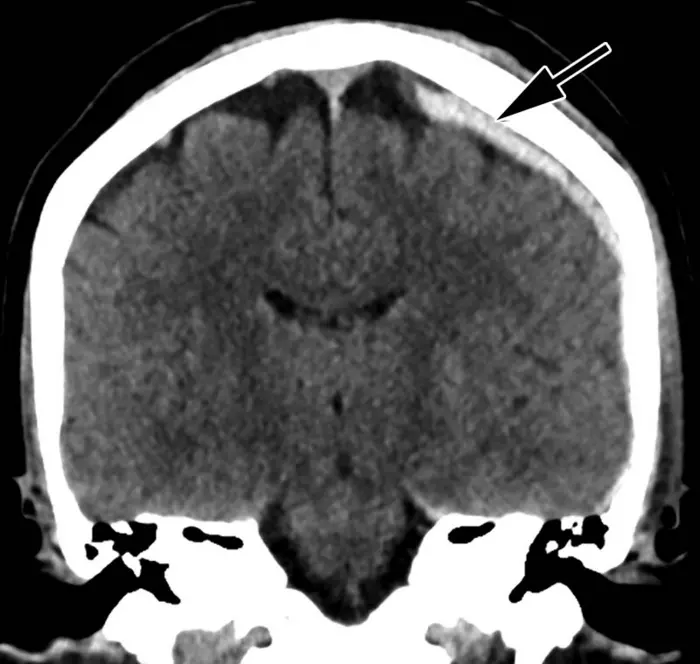

Head CT of intimate partner violence patient with left-sided parietal subdural hematoma (arrow).

Review of reports by two experienced emergency radiologists revealed that both intimate partner violence and suicidal behavior played independent roles in doubling the overall injury rate compared to that of patients without a history of intimate partner violence or suicidal behavior. Patients with intimate partner violence often sustained head, face, neck and upper limb injuries—areas commonly hurt during assaults.

Intimate partner violence patients with suicidal behavior suffered over six times as many head/face/neck injuries, almost four times as many spinal fractures, three times as many deep injuries, and twice as many upper extremity injuries. These patients experienced almost twice as many severe injuries and three times as many mild injuries.